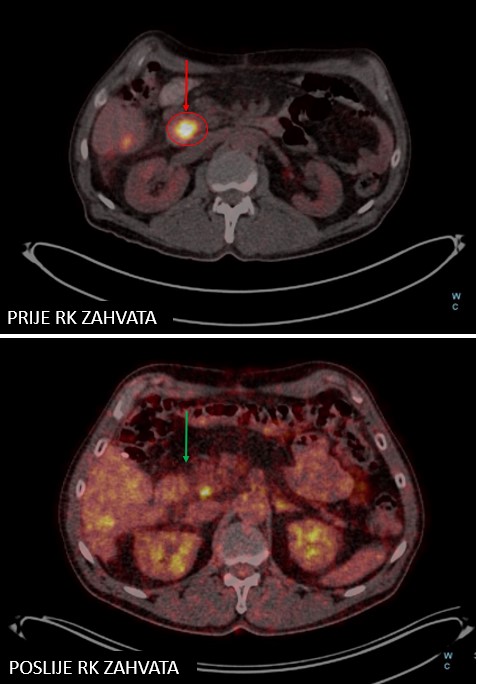

Rezultat – 24 mjeseca nakon RK

Potpuna metabolička regresija tretiranih lezija